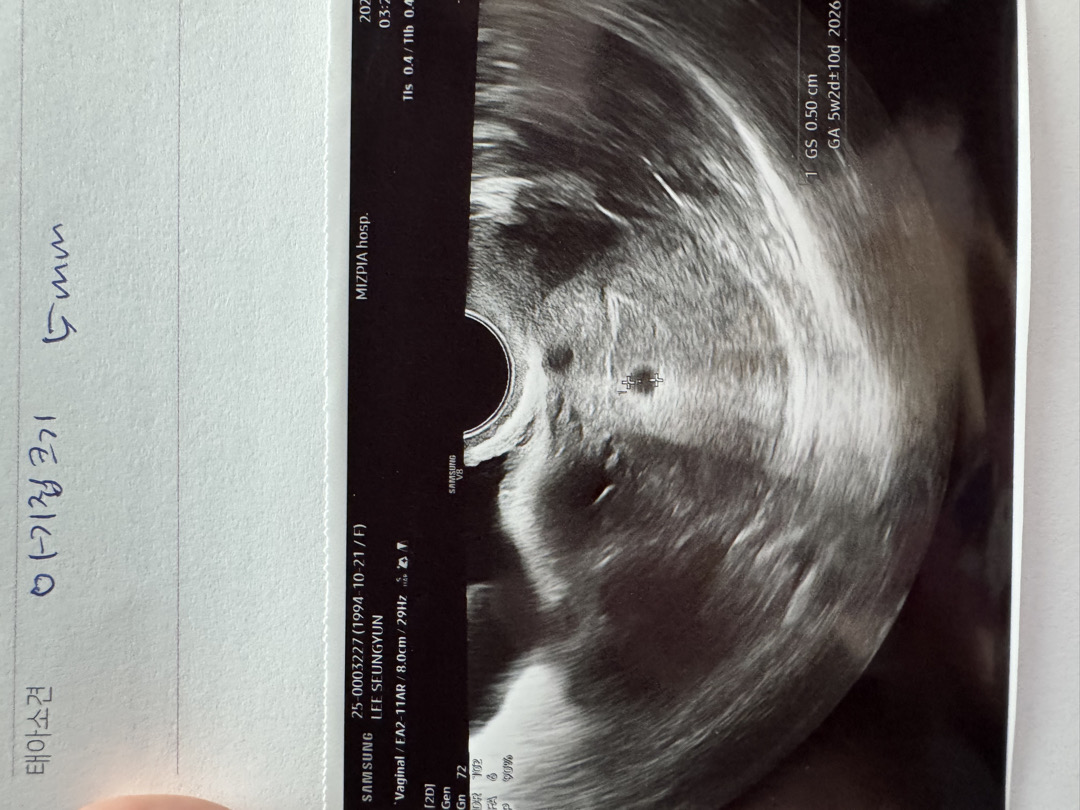

오늘 아기집초음파봤어요!!

저번주에 2mm이라서 임신 확인 못받고 오늘 감기가 너무 심해서 감기약 받을겸 갔는데 아기집 봤어요ㅎㅎ 단태아라고 했는데 위에 동그라미는 몰까여…? 설마.. 집이 하나 더 있는건 아니겟죠!!????

저렇게 사진상으로 선명한데 의사샘이 별 말씀 없으셨으면 쌍둥이는 아닐거예여 순간에 찍힌 빛이 안드는 구멍이라던지? ㅎㅎ

2개처럼 보이긴 하네요~~^^